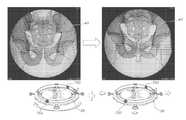

FIG. 7 is an illustrative embodiment of the displacement of the dimensioned pattern over the anatomy to quantify the rotation of the pelvis and thus the coronal plane of the patient.

FIG. 8 is an illustrative embodiment of showing the effective transposition of the patient sagital reference plane onto the machine with the use of the dimensioned pattern device.

Now referring toFIGS. 7-9, an anatomical image, such as an X-ray image, of apatient25 is acquired during a surgical procedure. Digital X-ray images are acquired intra-operatively, during surgical procedures such as joint replacements and trauma fracture reductions and deformity correction and implant placement/alignment. The acquired image can be viewed or further processed on a device, such as a computer with a monitor. A dimensionedradiopaque pattern40 specific to the anatomical reference for a known surgical procedure is attached to a medical imaging device such as a fluoroscopic or portable radiographic machine. In another illustrative embodiment, the dimensionedpattern40 is generated digitally on to the image. See U.S. Pat. Nos. 8,611,504, 9,456,874 and 9,610,134 hereby specifically incorporated by reference.

The intraoperative digital imaging allows immediate visualization of the bony anatomy of apatient25. The skeleton's anatomical landmarks for reference is well documented in medical textbook and literature. Using the image produced by the imaging machine as a non-invasive source of anatomical data, the dimensionedradiopaque pattern40, can be adjusted and used to align over pre-determined known anatomical landmarks. This allows a user to ensure and verify that the anatomical plane represented within the medical image is an accurate representation of the desired anatomical plane in the Z and Y axis.

The specifically spaced and quantified vertical elements of a dimensioned known pattern, are overlaid onto a AP Pelvis in the center of a 2D image. This allows auser27 to adjust the imaging machine or the position of the patient25 to adequately and accurately represent a patient specific rotated AP Pelvis view. This defines the coronal plane of the pelvis or the Z axis. The specifically spaced and quantified horizontal elements of a dimensioned pattern, overlaid on a AP Pelvis in the center of a 2D image, allows auser27 to adjust the imagine machine or the patient position to adequately and accurately represent a patient specific tilt in the AP Pelvis image. This defines the sagittal plane of the pelvis or the y axis.

The step of extrapolating the third axis from the 2D anatomical reference plane is shown. Once two axes have been identified, the surface of the imaging device becomes the parallel transposition of these two axes into space. As a result, the remaining axis can be identified as perpendicular to both these axes. At this point, a 3-dimensional reference plane, aligned accurately with the anatomy, is determined.